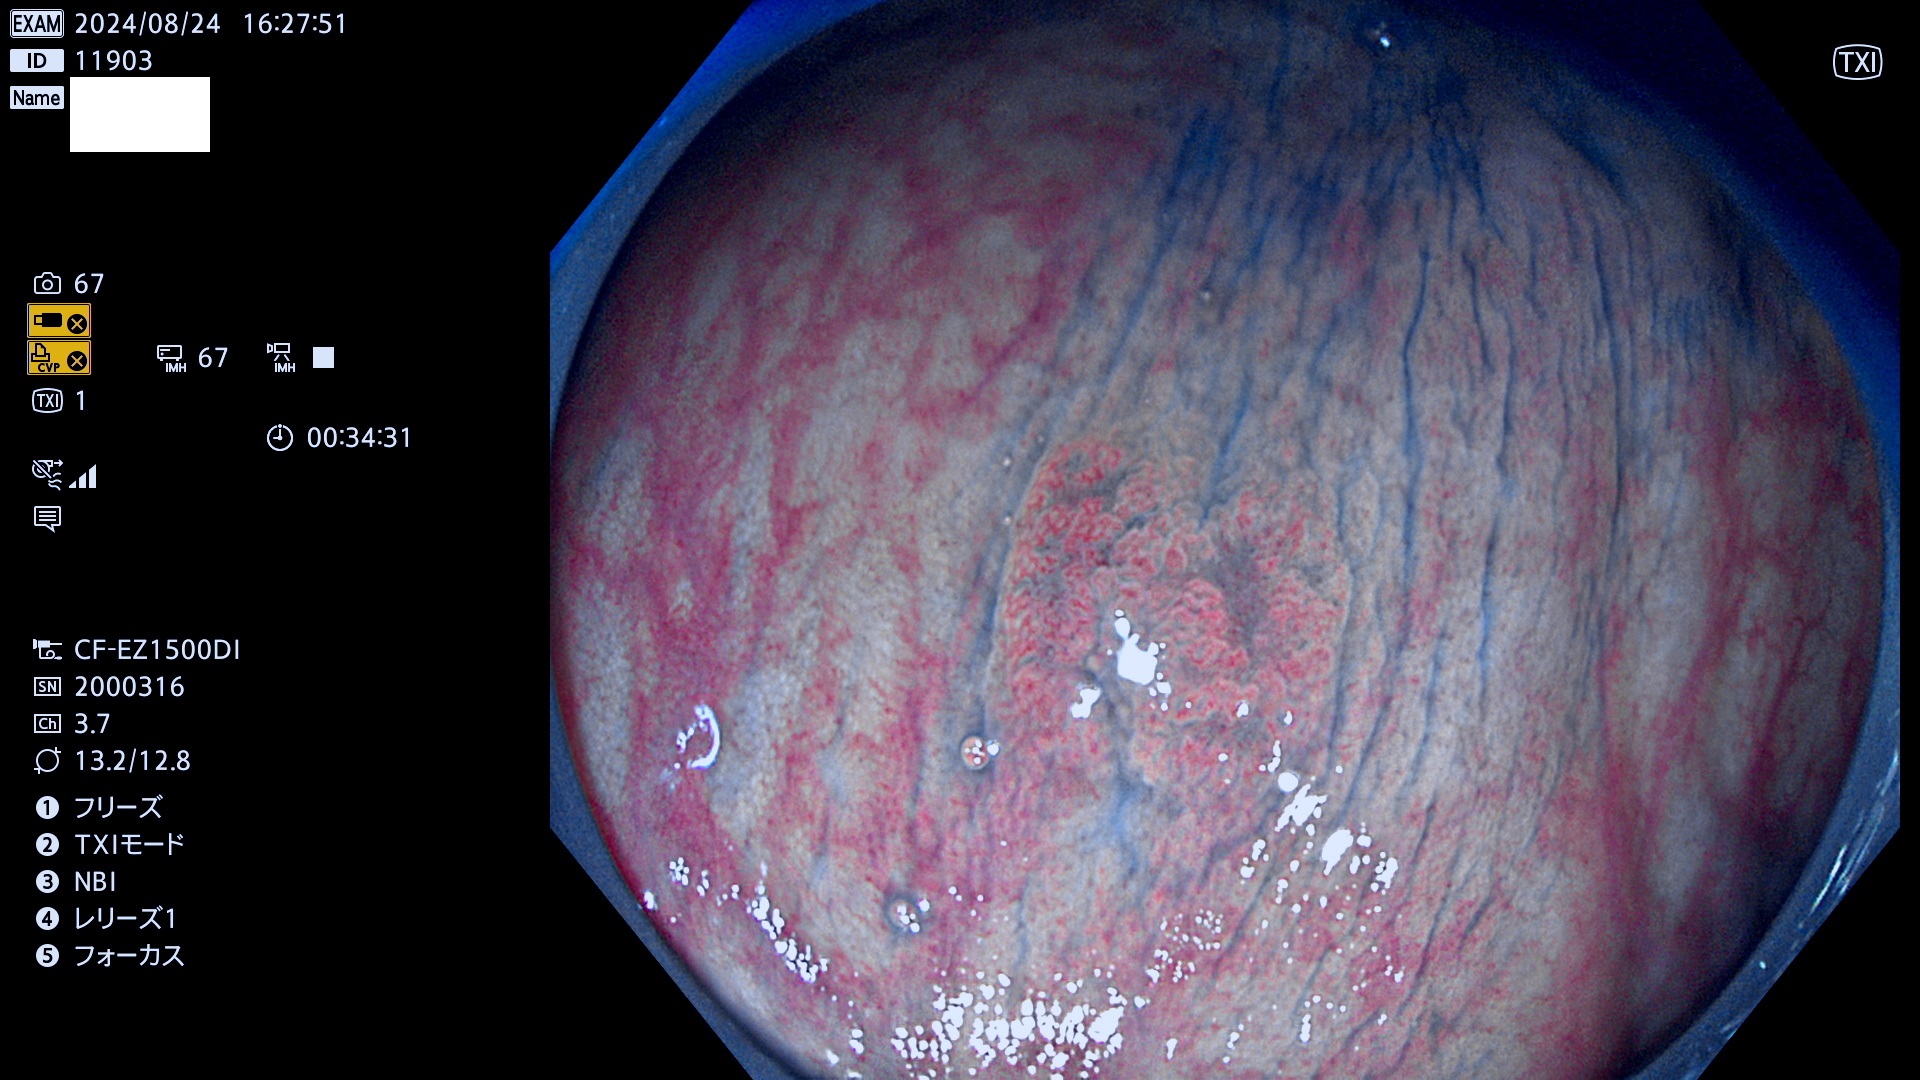

完全に平坦な物をUb、陥凹している物をUcと呼びます。最も発見が難しく危険な病変です。

毎週の検査(木・金・土・日)に発見されたUb、Uc型・腺腫を、その週の日曜の夜にUPし1週間、提示します。

抽出の対象期間 2024年8月22日〜8月25の4日間(33件の検査)7件 (7/33=21%)